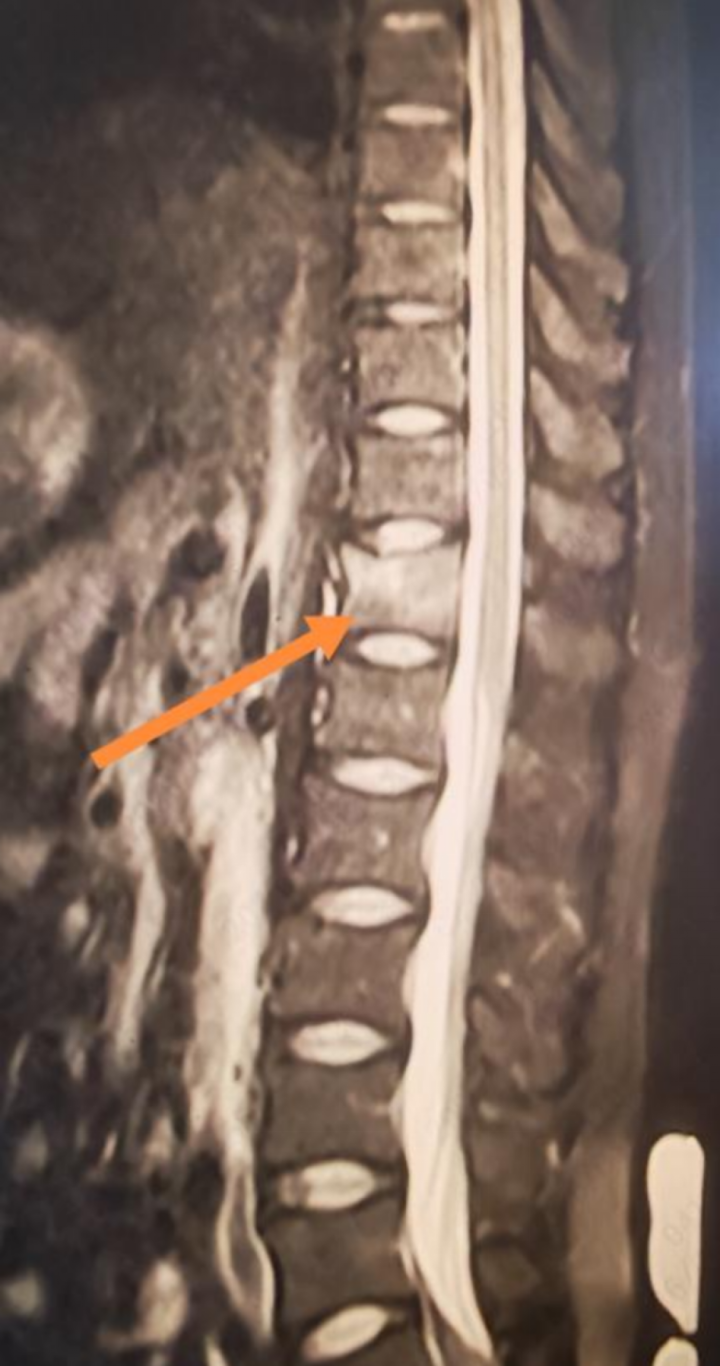

拿到核磁报告的那一刻,李先生彻底傻眼:胸12椎体压缩性骨折。

后续的骨密度等检查更让他连遭“暴击”:L1-L4的Z值仅为-3.1,这个数值意味着他的骨密度比大部分60岁老年女性还要低。一系列检查排除继发性骨质疏松后,骨代谢指标检查显示,李先生体内的维生素D指标仅为10ng/ml(化学发光免疫分析法,正常范围30-00ng/ml),远低于正常标准;同时成骨指标也存在明显不足,表明骨骼的生长和修复能力大打折扣。